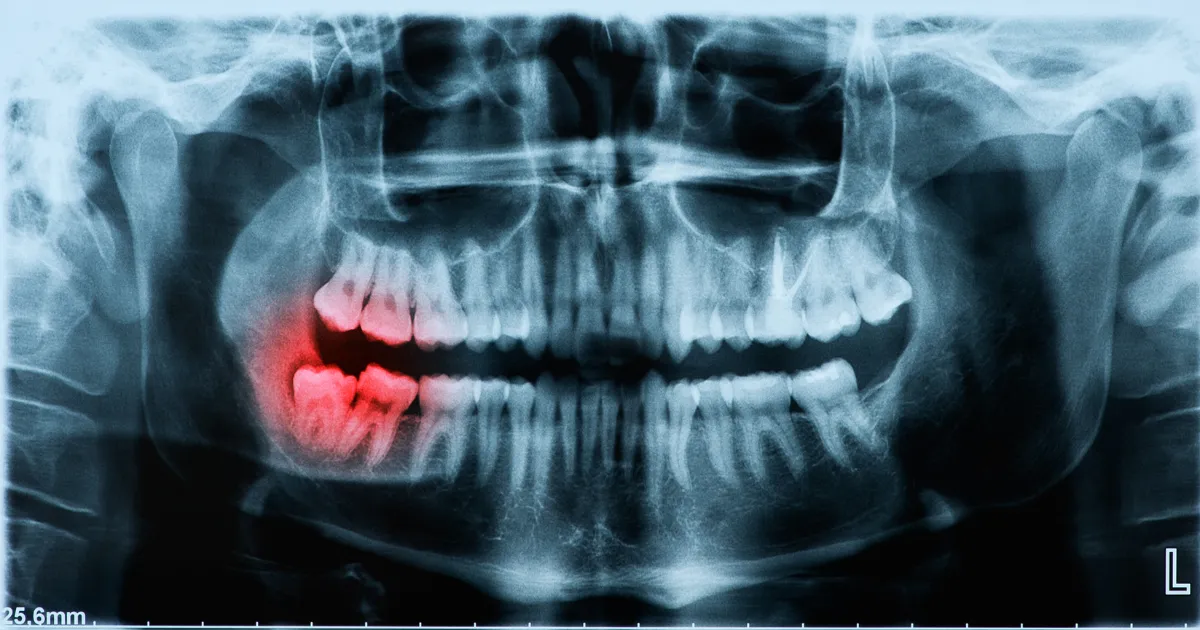

親知らずの生え方

斜めや横向きに生えている場合、シンプルに抜きにくくなりますので抜歯の難易度が高まります。

特に歯列に対して完全に水平に生えている場合、歯肉を切開したり歯冠の上に被っている骨を削る必要が出てきます。痛そうですね……